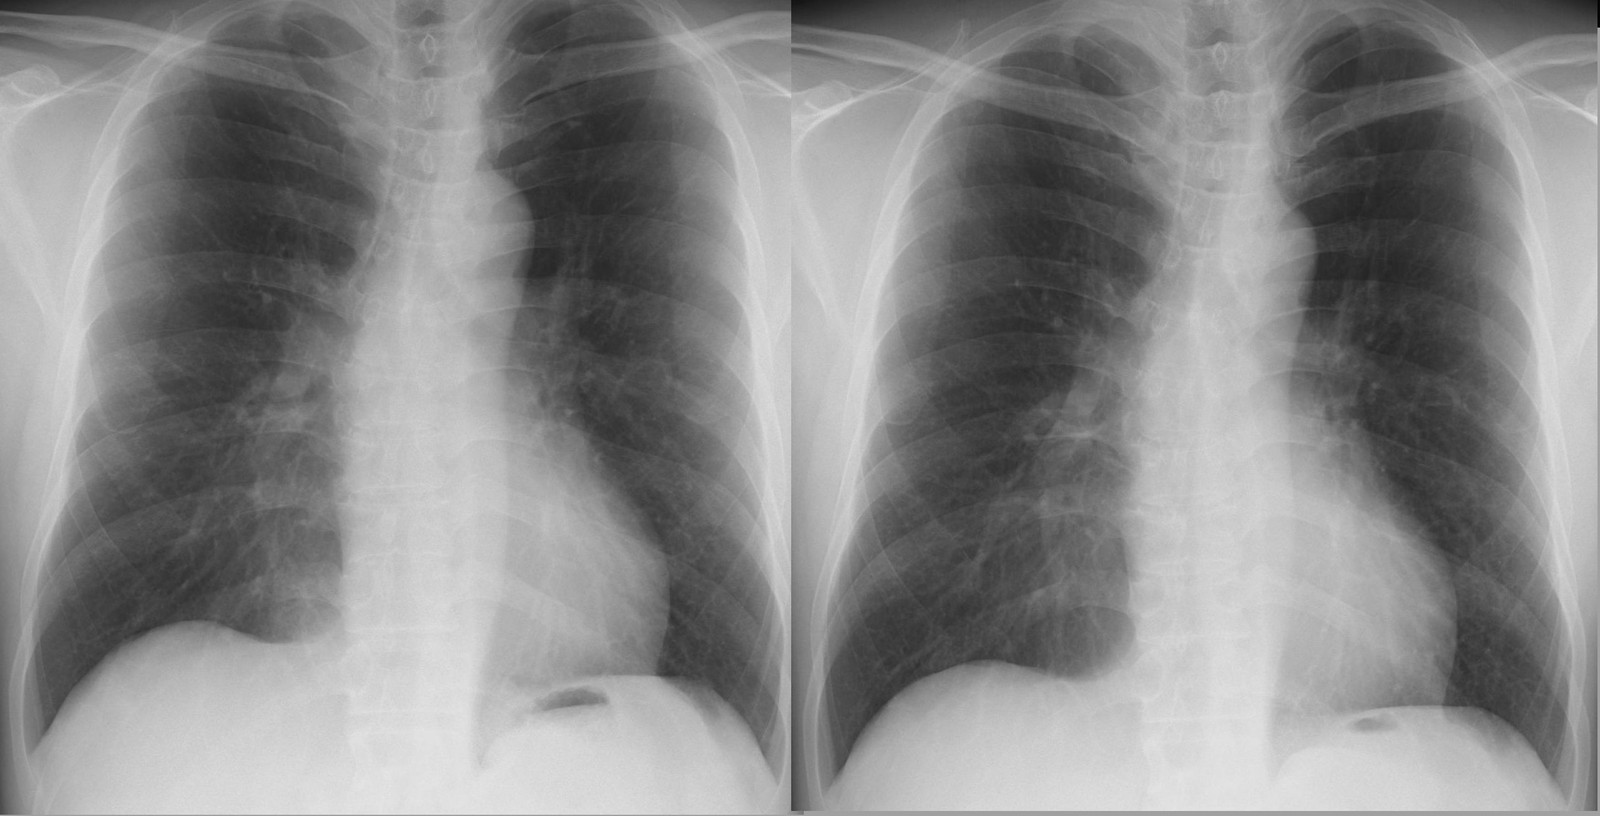

肺炎(写真右)を判断するとき、脂肪の不鮮明な陰影(写真左)との鑑別が難しい。横隔膜とのシルエットサインはある程度参考になるが以前のフィルムがあればより正確になる。 [心横隔膜角の脂肪組織と肺炎]②

*1~3の所見を今までの知識とシルエットサインをもとに読影すれば肺炎と判断できる。 比較するため治癒後のレントゲン像を示す。 [心外膜の脂肪組織は肺炎の陰影と紛らわしい]

①右写真は肺炎の浸潤陰、この場合は横隔膜のシルエットサインが参考になる。 ②下右写真は肺炎像、左写真は健康時のもの。この場合右写真心陰影のシルエットサイン陽性の部分が心下縁までには及んでないことが心外膜の脂肪としては説明がつかない。 自信を持って読影、ただし読みすぎないこと。